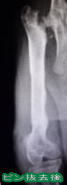

整形外科治療セット

小川病院 ; 完備   南台病院 ; 完備

パワードリル、マイクロエンジンをはじめ

骨折(プレートやピンの内固定)や脱臼、椎間板ヘルニアなど

の手術に必要な整形外科器械器具を各種取り揃えております。

※ レントゲン写真は当院での治療例です。

当院での整形外科手術による2023年9月時点の治癒率

(通常の歩行ができるようになった)は以下の通りです。

・骨折95%以上(2009年以降は100%)

・前十字靭帯断裂、膝蓋骨内方脱臼、股関節脱臼それぞれ100%

※この記載は治癒を保証するものではありません。